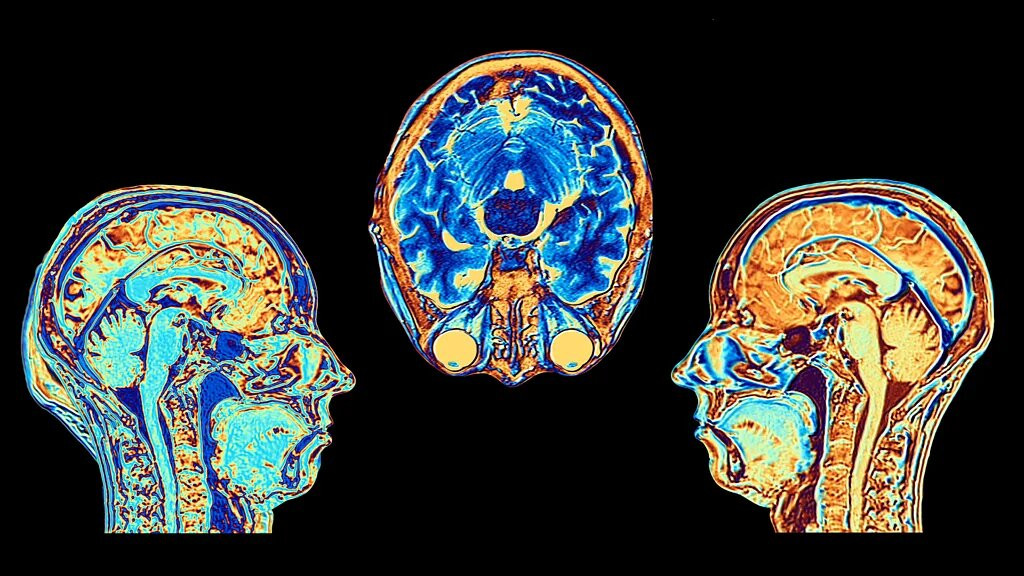

The locus coeruleus lies in the brain stem, just above the back of the neck – and contains around 50,000 cells, a tiny portion of the 86 billion neurons in the average central nervous system. Marie Antoinette's physician Félix Vicq d'Azyr was the first to note its existence in the late 18th Century – but for a long time, it failed to attract any further attention.

Across the night, we alternate between different sleep stages. There is "rapid eye movement" (REM) sleep, which – as the name suggests – is marked by the flickering of our eyeballs. It is associated with vivid dreaming and is thought to be crucial for processing and consolidating memories. Much of our rest, however, is spent in non-REM (NREM) sleep, during which the brain may engage in a deep clean, clearing away cellular waste that may lead to neuronal dysfunction if it is allowed to accumulate.

Measuring brain activity in dozing mice, Lüthi found that NREM sleep was associated with temporary bursts of locus coeruleus activity every 50 seconds. This seemed to galvanise the thalami, a pair of egg-shaped regions which lie in the middle of the brain and are involved in sensory processing. As a result, the animal was more sensitive to outside stimuli, like noises – without fully waking. "It's generating this state of enhanced vigilance," Lüthi says. "It really gives you this idea that wakefulness can be graded in the brain."